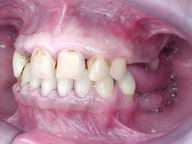

Reabilitação funcional e estética em ambas as arcadas

com próteses fixas e removíveis de encaixe de precisão.

ANTES

Vista Lateral Direita